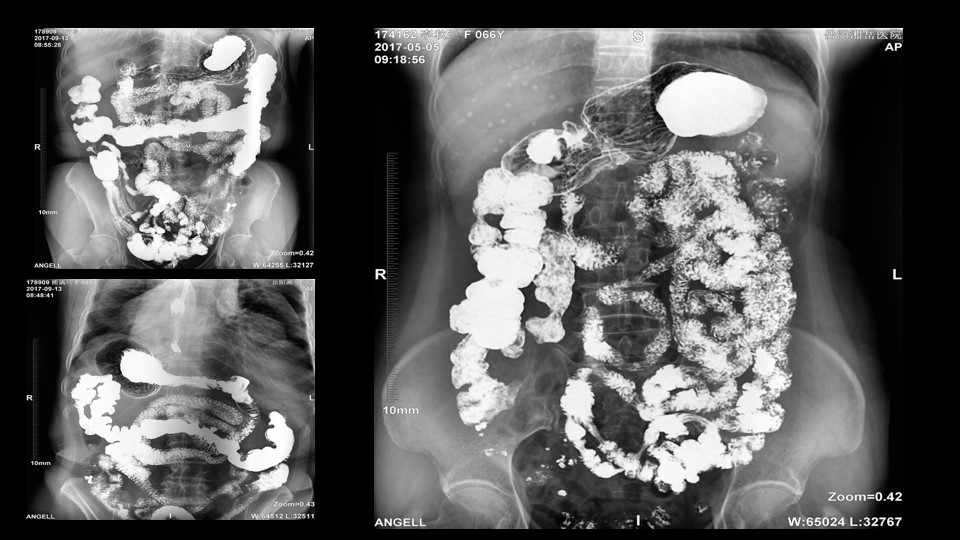

會議開始,岳陽市醫學會放射分會副主委、湘岳醫院放射科蔡雨主任,結合自身在放射影像的20多年經驗,為參會嘉賓分享了動態DR在消化道造影中的應用價值。作為動態DR用戶,蔡雨主任結合動態DR的實際拍片與操控經驗,分享了動態DR技術在相關群體疾病檢查上的獨到優勢和人文關懷。蔡雨主任說到:“隨著內鏡技術的發展以及CT、MR的發展,消化道造影在減少,但是這并不意味著消化道造影的價值在下降。以老年人為例,很多老年群體都患有嚴重的心肺疾病、或者消化道畸形,很多老年人本身就有糖尿病、高血壓等等綜合疾病,傳統內鏡的檢查對于這類群體來說是一件難以忍受的痛苦,而動態DR的多項創新技術讓這類群體的消化系統疾病篩查變得更為人性和精準。任何一個好的消化道造影,一定是患者、診斷醫生、臨床醫生三方滿意的結果。安健科技動態DR技術利用900萬像素高清拍片、大幅面透視、高清點片、視頻保存與回放等核心功能,完全滿足臨床對消化道氣鋇雙重造影檢查的需要。圖像質量全面超越以往模擬胃腸機、影增數字胃腸機”。蔡雨主任全面演示了動態DR在食道造影、上消化道造影、小腸雙對比造影、結腸氣鋇雙對比造影中的應用,通過動態DR可以清晰獲得臨床診斷和評估的圖像依據。

▲蔡雨主任使用動態造影圖像示例